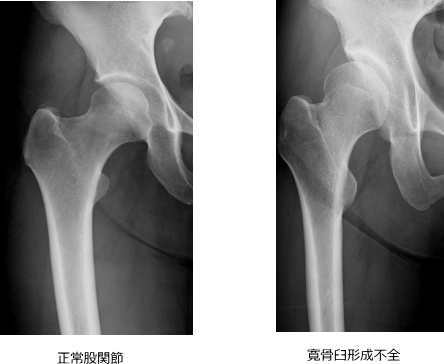

股関節は、骨盤と大腿骨をつなぐ関節です。骨盤側の「寛骨臼(かんこつきゅう)」がお椀のような受け皿になり、太ももの骨の先端である「大腿骨頭(だいたいこっとう)」が球状にはまることで滑らかな動きを可能にしています。

1.寛骨臼形成不全

股関節の受け皿が浅く、大腿骨頭を十分に覆えていない状態です。

日本人女性に多く、変形性股関節症の約9割がこれに関連しています。

この状態では、関節の一部に負担が集中し、軟骨の摩耗が進行します。